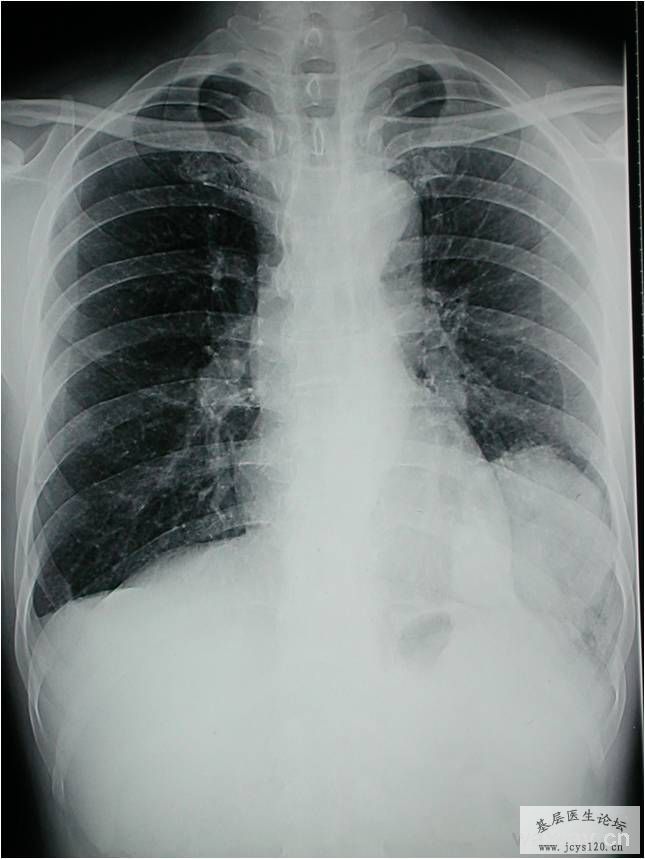

男,55岁,反复咳嗽2月余;2个月前无明显诱因出现咳嗽,无发热、咳痰、胸痛,无夜间盗汗、乏力等症状